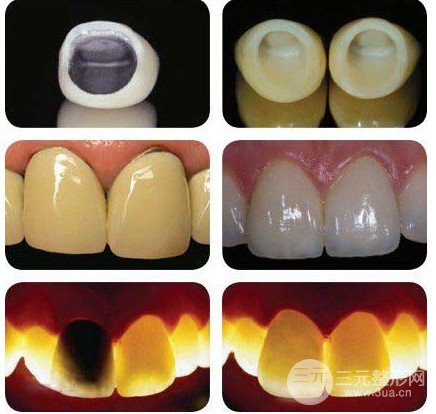

烤瓷冠全称烤瓷牙熔附合金全冠,也称合金烤瓷牙全冠,是一类由瓷熔附到锻造合金基底冠上的金—瓷复合结构的修复材料。简单讲,就是里头是一个合金底冠,外边上1层瓷,因此它兼顾合金的抗压强度和瓷的美观大方,在较长一阵子深受求美者和大夫的钟爱。

在预算充裕的条件下,因为全瓷牙的内冠不再应用金属材料,而选用与牙齿色彩相仿的高强度瓷材料做成,因而较金属材料来说,瓷的修复体更美观,半透明度与天然牙近似,修复后牙床边沿呈现更为自然,可做到模拟仿真作用,外观就更像自然牙。此外,全瓷牙对附近结构无刺激,传热低,不导电,抗磨损且人体适应性好,物理性能和美观性能都好于烤瓷牙,同时对头部和脖子的磁共振检测没有影响。